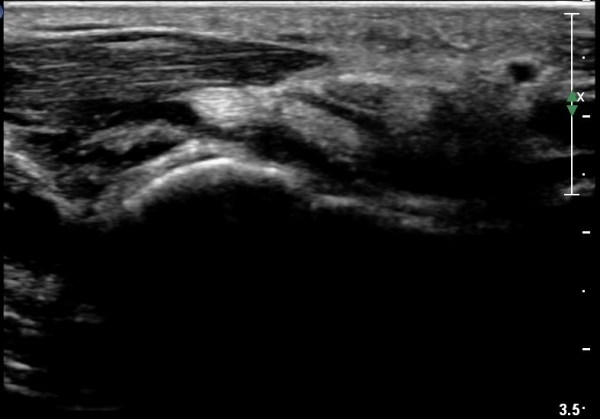

¼Õ¸ñÀÇ È¾´Ü¸é°Ë»ç¿¡¼­ Á¤Á߽ŰæÀÇ ºÎÁ¾ µî ƯÀÌ ¼Ò°ßÀÌ º¸ÀÌÁö ¾Ê´Â´Ù(»çÁø 1).